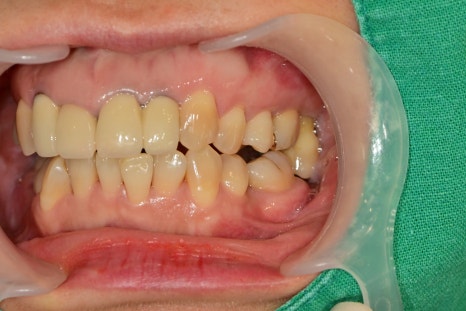

치과치료가 두려워서 치료를 미루고 계셨던 환자분께서 가족소개로 내원해 주셨습니다.

아래 어금니가 3개가 발치된 상황에서 오랜 시간 지남에 따라 아래쪽은 어금니가 쓰러져있었고,

위쪽 치아는 아래에서 서포트해주는 치아가 없기 때문에 아래쪽으로 정출되어 있는 상태였습니다.

치아의 쓰러짐과 정출된 정도가 너무 심했기 때문에 임플란트 수술을 위해서 해당 치아들의 발치가 불가피했습니다.

큰 용기를 내주어 내원한 환자분께 현 상황에 대해 자세히 설명드리고, 한쪽씩 나누어 치료를 진행하기로 했습니다.